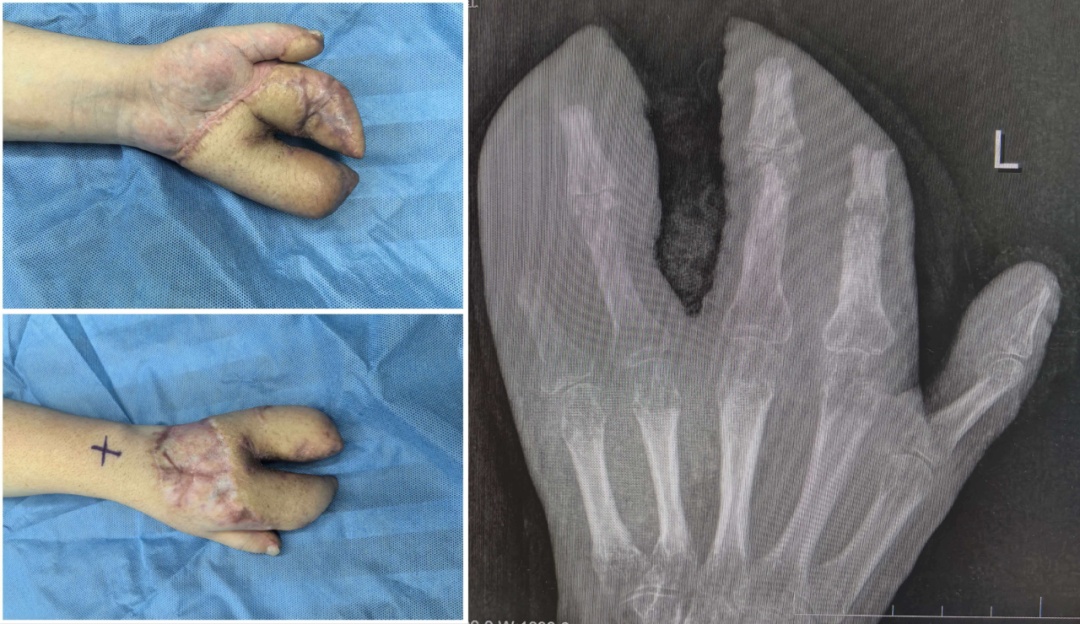

术中,医生们完成了彻底的清创,并像修复精密仪器一样,修复了骨折、断裂的肌腱与神经。

为覆盖巨大创面,医生启用了经典的“腹部带蒂皮瓣”,将小王的断手“寄养”在了带有自身血供的腹部皮肤上,为后续所有修复提供了生存的土壤。

经过近一个月的“腹手相连”,皮瓣在手部建立了新的血运。医生们进行了“断蒂”手术,让手从腹部独立。

完美的指蹼(手指间的缝隙)是手指灵活张开与并拢的关键。随后,医生们开始功能重塑,通过2次分指与指蹼重建术,把粘连在一起的手指分开,重建出更自然、更深的指蹼。